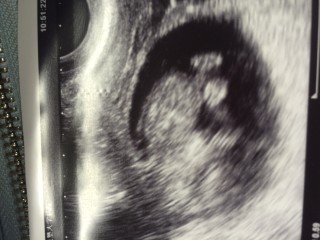

順調に育ってました!CRL28.7㎜です♪ 手足がバタバタ動いてかわいらしかったです! まだまだつわりは酷く、毎日嘔吐してます。 つわりは折り返し地点まできている様子少しずつ軽くなるといいなあ。

妊婦健診一回目に行きました! つわりがピークで辛い… 9wに妊娠悪阻で5キロ減り点滴に通い、10wで水は何とか飲めるように… 赤ちゃんの様子が心配でしたが、心配をよそにスクスク育ってました(*^^*) 29.8mmの赤ちゃん!手足も長くなってて、頭もまんまる(*^^*) へその緒も確認できました! 次の検診は一ヶ月後…我が子の姿が見れるのも一ヶ月後… 長いですが、つわりと戦いながら頑張ります!